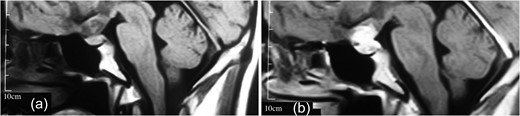

(a, b) MRI revealing a well-delineated round tumor 30 × 25 × 20 mm in diameter, T1W isointense and T2W hyperintense lesion located within the sella turcica and another dural-based lesion lying over the diaphragm sella extending to the planum sphenoidale. The intrasellar lesion showing a faint enhancement after contrast material injection but the suprasellar lesion has a bright enhancement.